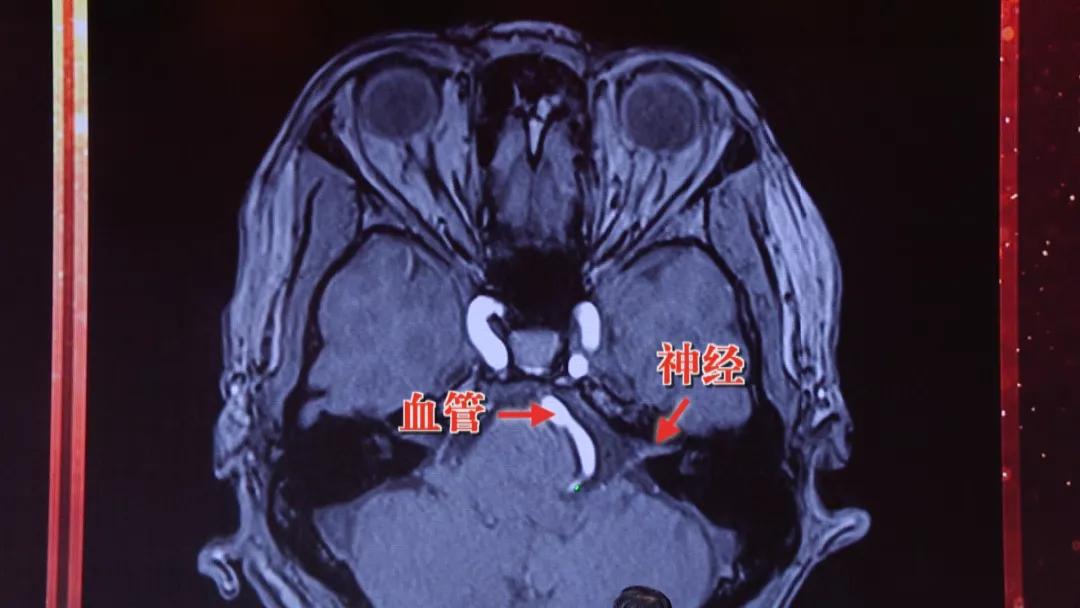

通过磁共振检查,如果有特殊的高血压,那么可以发现血管压到了神经,而普通高血压没有这种发现;另外特殊高血压伴随表现为 眼皮跳、脸疼 。

导致这种特殊高血压的原因,其实是 脑子里的血管压迫到了迷走神经区域 ,才会出现久治不愈的高血压,如果同时压迫到 面神经 ,就会出现 眼皮跳 等高血压的伴随症状。